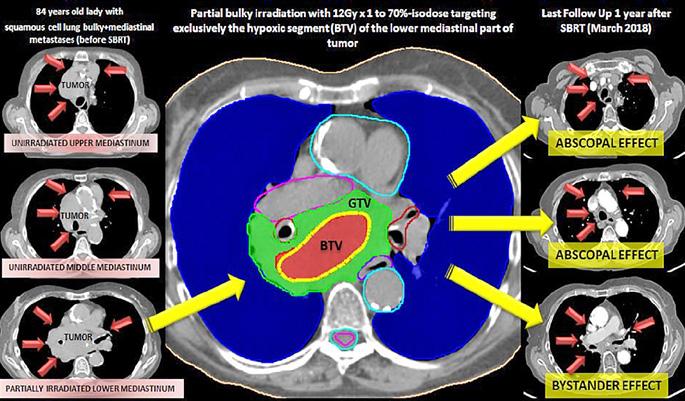

Figura 1. Leziune decelată colonoscopic la 25 cm de OA Figura 2: Îngroșare parietală asimetrică la nivelul joncțiunii recto-sigmoidiene Figura 3. Adenocarcinom moderat diferențiat, cu arhitectură tubulară